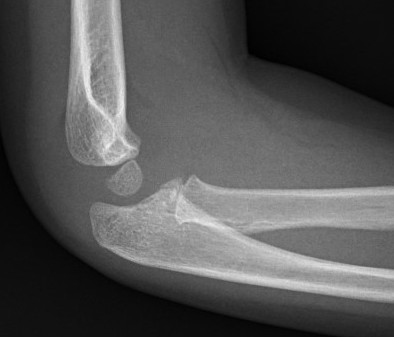

Case 2. Chronic Monteggia with deformed radial head